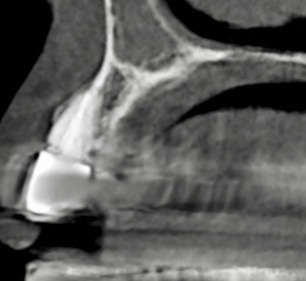

骨量不足でこのままではインプラント治療をお受けできない場合など専門性高い治療を当医院ではお受け致しております。